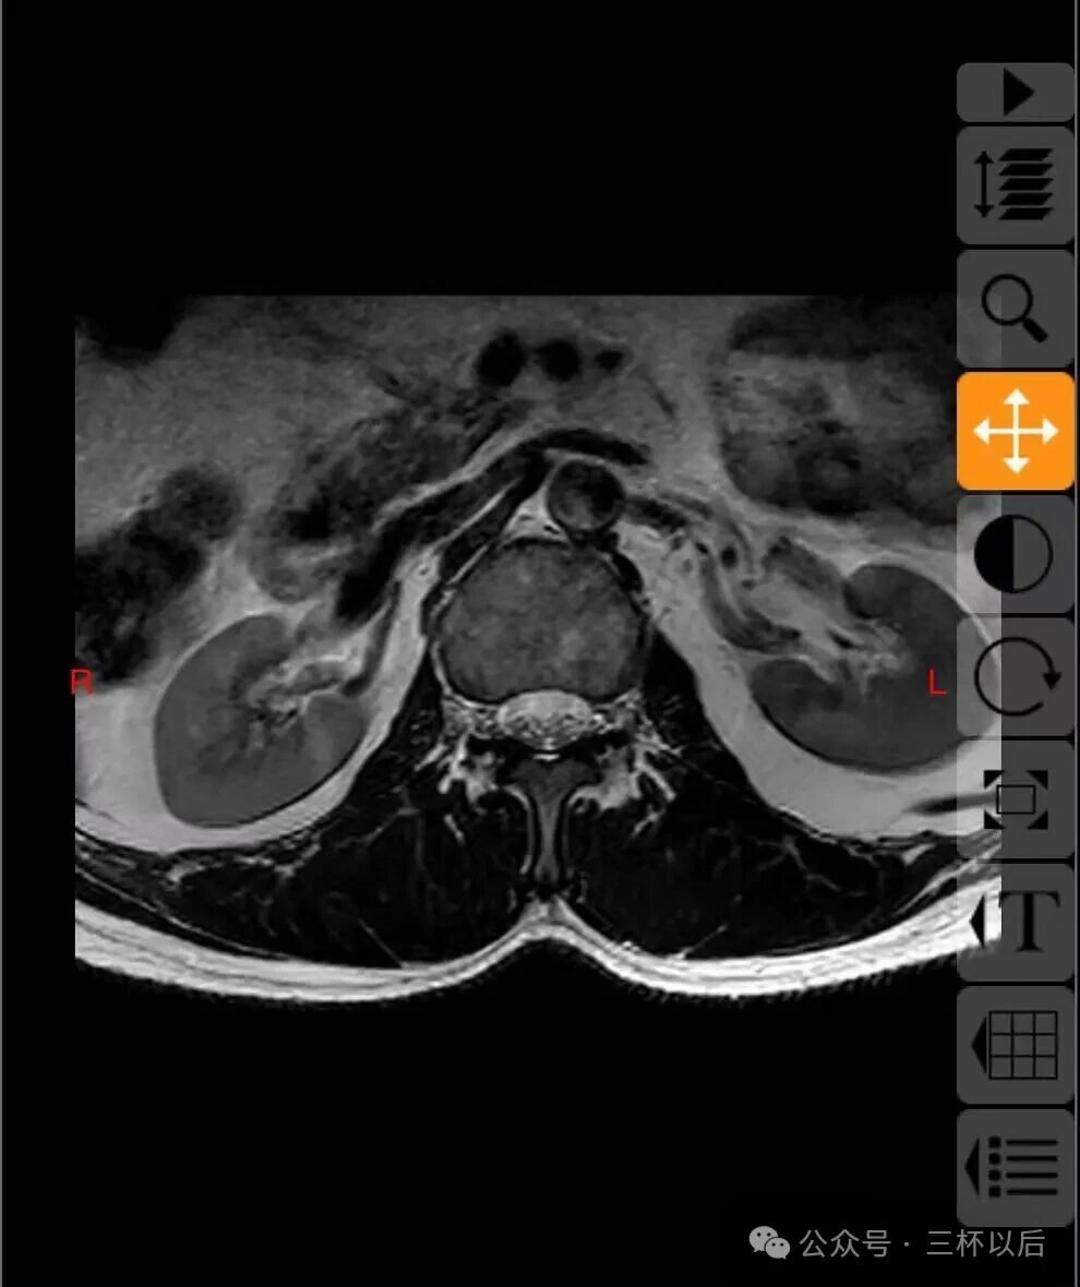

前两天排队做了核磁检查,今天又挂了号让医生给看下,结论腰是有问题,不过没有大问题,避免久坐,久站,做核心力量训练。我问可以打羽毛球,跑步,游泳吗?说可以,不影响。不过我的印象中,之前腰疼的时候打羽毛球,晚上8—10点,结束之后,一晚上疼的没怎么睡好,从那之后就暂别了打了十年的羽毛球运动。

心里多少踏实一些,自从2024年10月份开始腰疼,到现在已经一年半了,现在腰疼真的是如影随形的,心里总是嘀咕,严肃医疗,江湖郎中,各种办法都用了,心里想着是不是可以治愈,恢复到以前的正常状态,现在看是不现实的,即便是我努力加强运动也只是代偿,仅此而已。

顺便贴一下拍的片子,如果有懂行的欢迎给我建议,我听劝的。真真希望能恢复如初,现在每天都能感受到疼痛,用了各种办法也不管用。